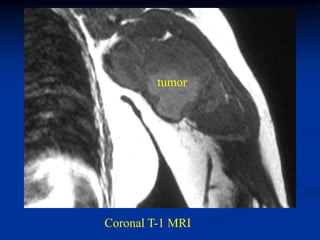

Case #1198.3            CT scan 4/06

09

Sag T-1        Gad

Axial T-1 upper   T-2 upper

T-2 lower         Cor STIR